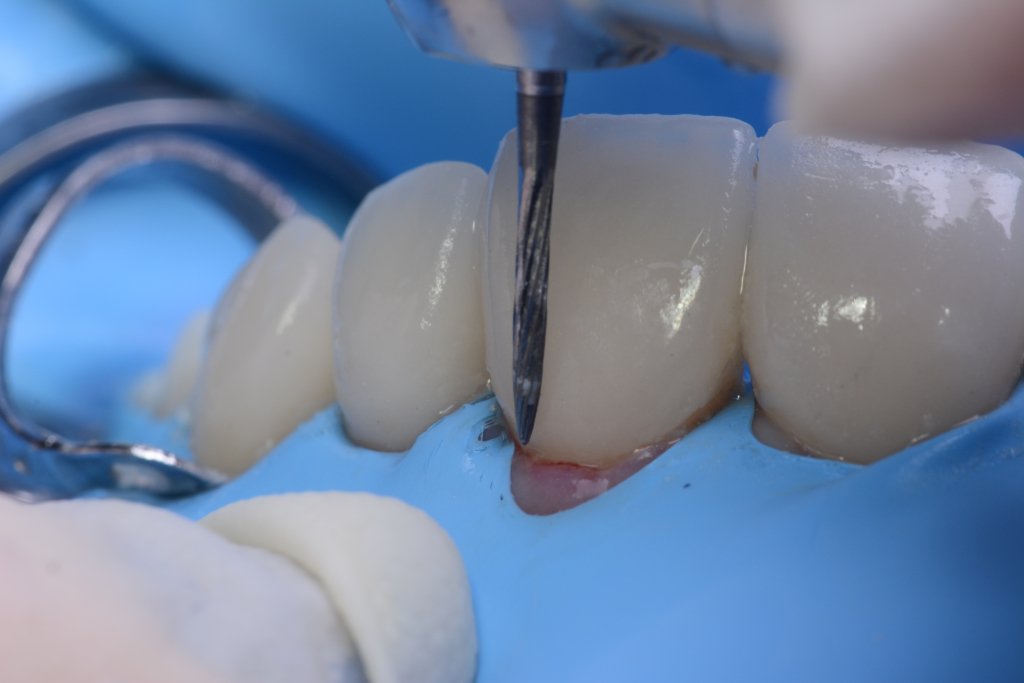

Y vamos de Azul (NIC TONE) sin linea de terminación, sufrimos el doble..no tenemos donde agarrar el Clamp y sobre todo donde realmente termina la carilla…

Voy siempre de 2 en 2, claramente cemento antes las Coronas, que me ayudaran a «clampar» y luego las carillas. Pero normalmente empiezo con los laterales que están en el medio y suelen robar el espacio a los otros